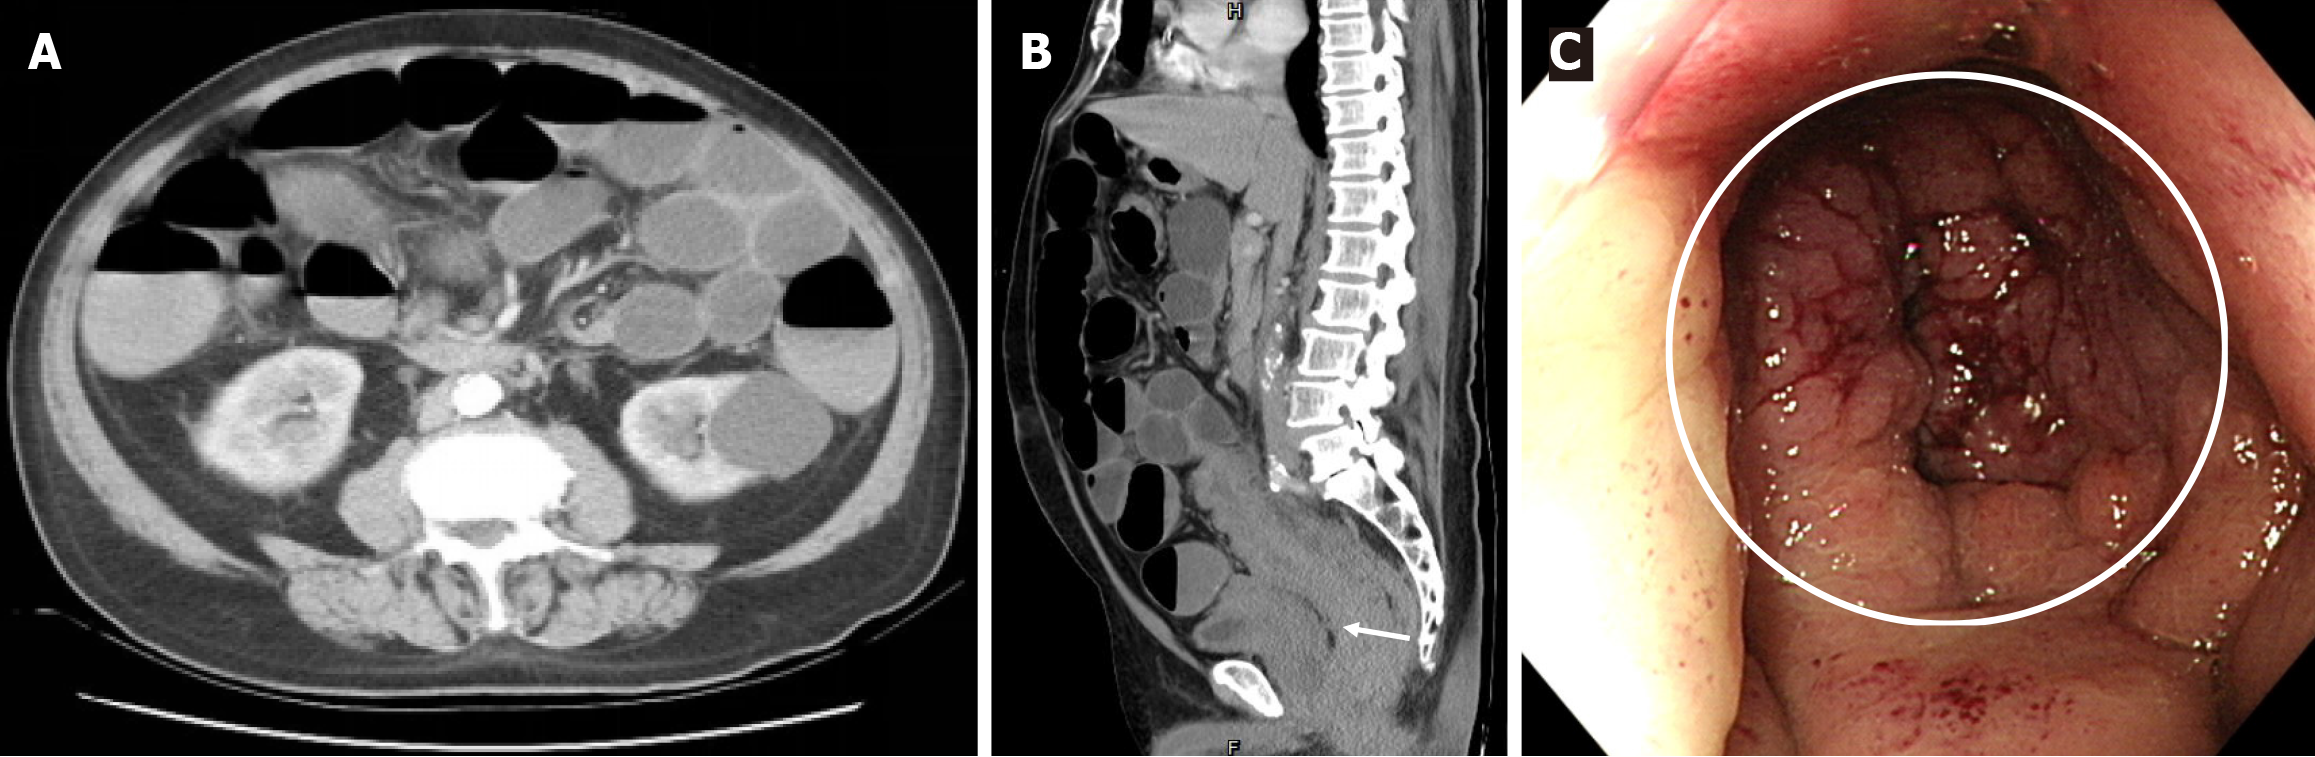

Figure 1 Preoperative evaluation.

A: Diffuse distension of the small and large intestines on axial-view abdominal computed tomography; B: Long segmental thickening of the rectosigmoid colonic wall and perirectal fat stranding with a clear vesicorectal fat plane (white arrow) on sagittal-view abdominal computed tomography; C: Obstructed lumen with mucosal swelling (white circle) located up to 5 cm from the anal verge on colonoscopy.